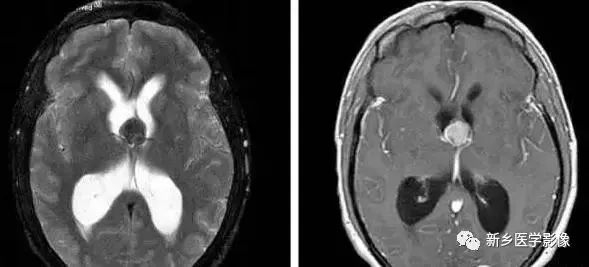

❶ 导水管狭窄

中脑导水管是脑室系统最狭窄的通道,也是脑脊液循环受阻最常见的部位。

导水管粘连主要见一于颅内感染和出血后,可于胚胎期发生,也可见于出生后任何年龄。导水管粘连所致狭窄多位于导水管远端。狭窄段长度通常为2一5mm,狭窄近端异水管可呈喇叭口样扩张。

导水管狭窄时,三脑室扩大常很显著,三脑室前部视隐窝和漏斗隐窝扩张或消失,三脑室后部松果体隐窝和松果体上隐窝明显后突,向小脑上池疝入。严重者可压迫小脑。

❶ 交通性脑积水

又称脑室外梗阻性脑积水,是由四脑室出口以后脑脊液循环通路障碍所致的脑积水。常位于蛛网膜下腔,以基底池最常见。

主要原因包括脑膜炎、蛛网膜下腔出血、脑膜转移、外伤、静脉窦血栓、颅脑手术后和脑脊液吸收功能障碍等。临床表现主要由颅压增高所引起.,可表现有头痛、呕吐、复视和视乳头水肿等。

交通性脑积水时,第四脑室扩大通常出现较晚,故早期时,可仅表现有侧脑室和三脑室扩大。主要应与导水管狭窄之梗阻性脑积水区别。MR矢状位T1加权图是直接观察导水管有无狭窄的最好方法。